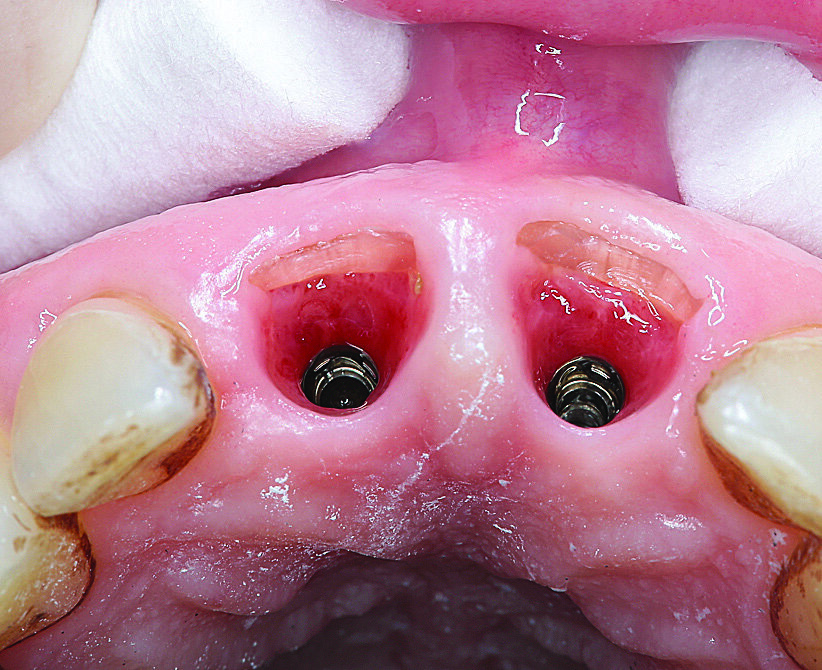

Odmah nakon implantacije postavljen je laboratorijski izrađen privremeni nadomjestak koji je uz pomoć privremenih nadogradnji pričvršćen na implantate 12 i 22. Na postoperativno snimljenom ortopantomogramu uočava se pravilan položaj implantata (Slika 7.). Sljedećeg dana nakon implantacije pacijent je došao na kontrolni pregled. Rana je bila bez znakova upale i simptoma. Na Slici 8. vidi se stanje prvog dana postoperativno i vestibularni fragment zuba. Nakon dvanaest dana uspostavila se stabilna arhitektura sluznice s vestibularnom ljuskom (Slika 9.).

Slika 8. Prvi dan postoperativno: vestibularna ljuska jasno je vidljiva

Slika 9. Dvanaest dana postoperativno: stabilne arhitektura sluznice i vestibularna ljuska